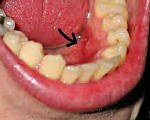

Рак полости рта. Злокачественное новообразование, происходящее из эпителия и мягких тканей ротовой полости. На ранних стадиях протекает бессимптомно, представляет собой узелок либо язвочку. В последующем рак полости рта увеличивается в диаметре, появляется боль, сначала локальная, потом - иррадиирующая в голову и уши. Усиливается слюноотделение. При распаде возникает неприятный запах изо рта. Часто присоединяются вторичные инфекции. При лимфогенном метастазировании отмечается увеличение регионарных лимфоузлов. Диагноз выставляют с учетом данных осмотра и биопсии. Лечение - радиотерапия, оперативное удаление, химиотерапия.

С учетом особенностей роста опухоли различают три формы рака полости рта: язвенную, узловатую и папиллярную. Язвенная форма - самая распространенная, проявляется образованием медленно или быстро растущих язв. Узловатый рак полости рта по внешнему виду представляет плотный узел, покрытый беловатыми пятнами. При папиллярных новообразованиях в ротовой полости возникают быстро растущие плотные выросты.

На ранних стадиях болезнь протекает бессимптомно либо проявляется скудной клинической симптоматикой. Пациенты могут замечать необычные ощущения в полости рта. При внешнем осмотре выявляются язвочка, трещина или участок уплотнения. Четверть больных раком полости рта предъявляет жалобы на локальные боли, объясняя появление болевого синдрома различными воспалительными заболеваниями носоглотки, зубов и десен. При прогрессировании онкологического процесса симптомы становятся более яркими. Боли усиливаются, иррадиируют в лоб, ухо, скуловые или височные области.

Рак дна ротовой полости на ранних стадиях протекает бессимптомно. Пациенты обращаются к стоматологу после выявления опухолевидного образования, ощущаемого, как безболезненный нарост. Рак полости рта рано прорастает близлежащие ткани. При прогрессировании поражаются регионарные лимфоузлы, возникают боли и усиленная саливация. Возможны кровотечения.